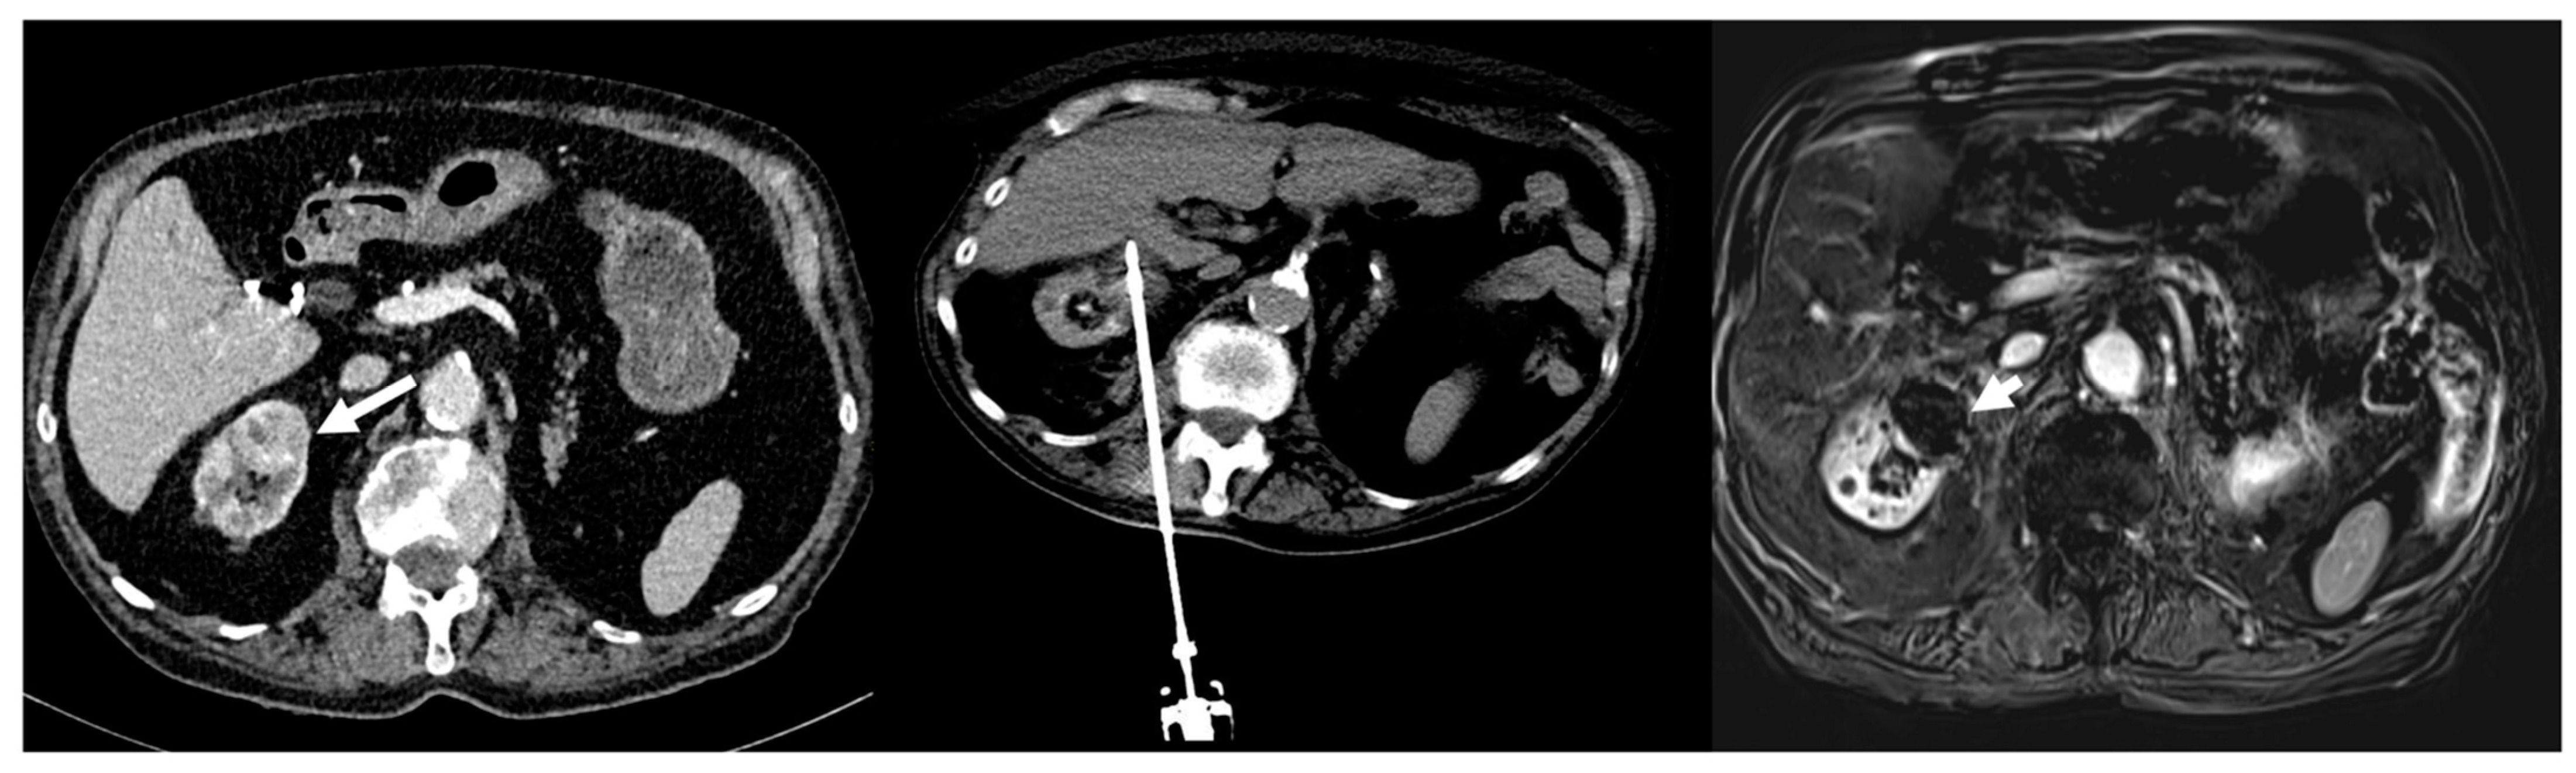

Figure 2.

Eighty-five-year-old man with 3 cm biopsy-proven clear cell renal carcinoma (image left, white arrow)). RENAL nephrometry score calculated as 6. The central image shows the CT scan obtained with the patient in a prone position and the cryoprobe placed in the tumor with the final ice ball (end of the second freezing cycle). The right image shows the MRI during follow-up at 1 month, demonstrating complete local response with no evidence of tumor enhancement (white arrow head).